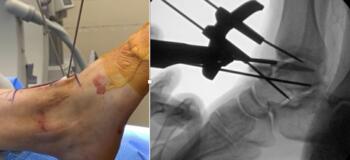

The incision was the typical anterior ankle approach. This would limit location of incisions for potential future issues or conversion to fusion or total implant. We then exposed the distal tibia and dorsal neck of the talus. Placing the prefabricated custom cut guide onto the neck of the talus, we then checked this under fluoroscopy to ensure placement, and the proper orientation and amount of lateral dome to be removed. We then pinned this guide in place with predetermined holes. A reciprocating blade limited blade excursion and minimized potential for injury to adjacent structures. After removal of the damaged piece of talus we placed the trials. The goal was to have the trial flush or even slightly recessed with regard to the adjacent cartilage. During weight bearing, the native cartilage will compress, so it is important to match the weight bearing level. If the implant is proud, then during weight bearing the cartilage will naturally compress, but the implant will not, potentially giving rise to issues with load bearing around the device.